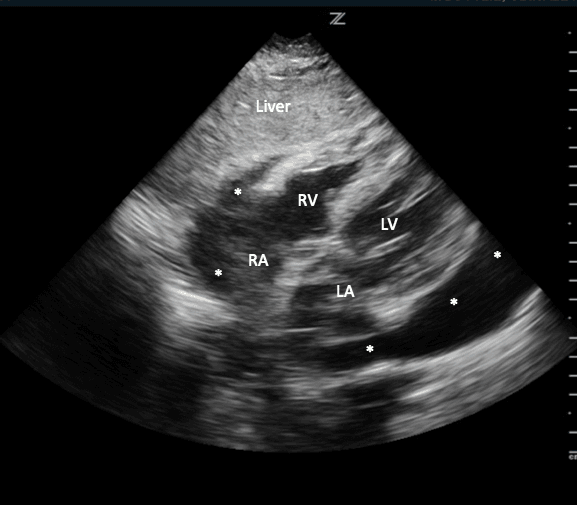

Use the liver as an acoustic window to enhance the image. The top of the screen will show the patient's liver. Immediately inferior to the liver will be the patient’s right ventricle and below this one can identify the left ventricle. Depending on the angle, one may also be able to visualize the right and left atrium in this view as well (Image 13).

Subxiphoid Labeled Structures